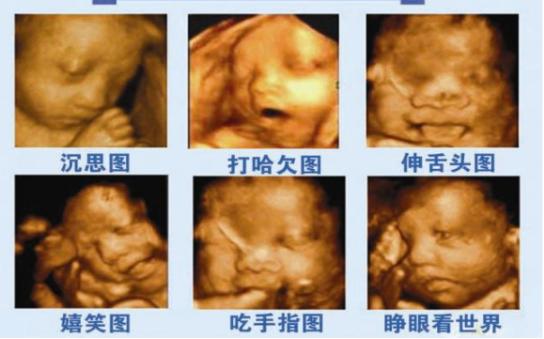

孕期需要做很多检查,其中四维大排畸就是很重要的一项检查,主要检查胎儿发育情况,四维比普通B超照的清楚,能够清楚看到胎儿在妈妈肚子里做什么。

胎儿在妈妈肚子里的生活也很精彩,有时候会吃吃小手,啃啃脚丫,还会吞咽羊水,打嗝,无聊的时候,脐带也是宝宝的玩具,哦,对了,小宝宝在妈妈肚子里还会小便哦!